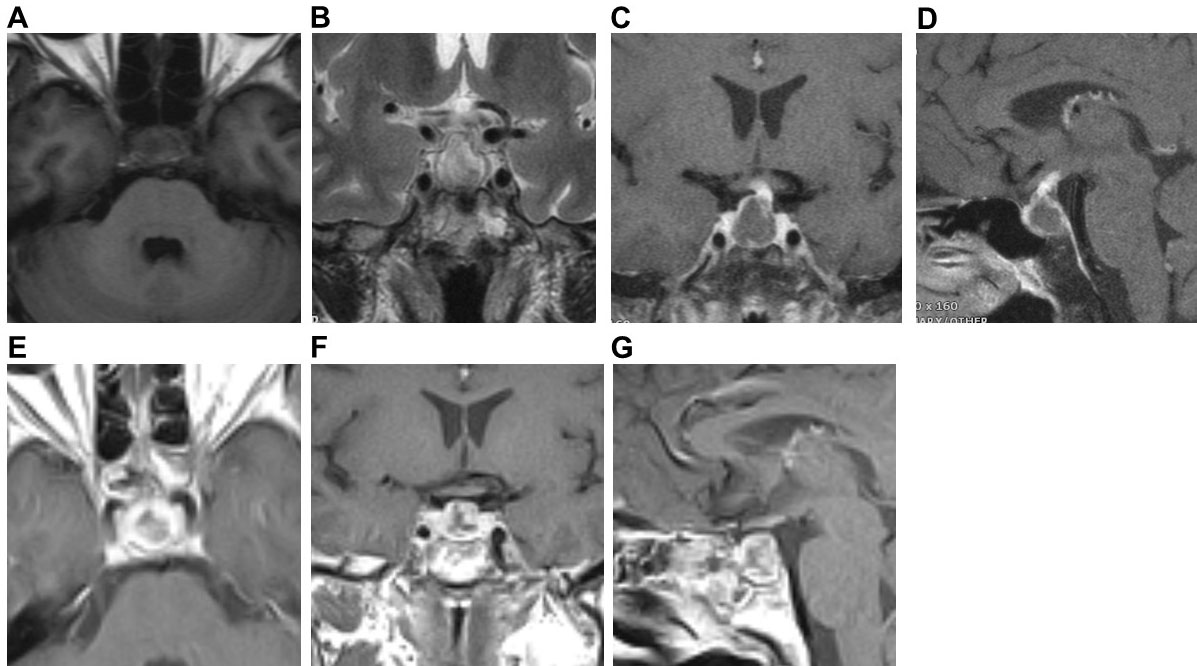

Fig. 1.

Fig. 1.Preoperative pituitary MRI and postoperative CT of Case 1. Preoperative coronal (A) and sagittal (B) MRI scans showed cystic lesions in the sellar. Both T1WI and T2WI were isointensity. There were sellar bone resorption and thickening of nasal septum mucosa. Preoperative coronal (C) and sagittal (D) enhanced MRI scan showed ring enhancement of the cyst wall, thickening and enhancement of the pituitary stalk, enhancement of the dura mater on both sides of the temporal lobe and petroclival region. Postoperative CT (E) showed no recurrence of the pituitary abscess.

Fig. 2.

Fig. 2.Preoperative pituitary MRI and postoperative MRI of Case 2. Preoperative axial (A) and coronal (B) MRI scans showed cystic lesions in the sellar, T1WI low signal, and T2WI slightly high signal. Preoperative coronal (C) and sagittal (D) MRI enhanced scan showed ring enhancement of the cyst wall, thickening and enhancement of the pituitary stalk, and bilateral cavernous sinus enhancement. Postoperative axial (E), coronal (F), and sagittal (G) MRI showed no recurrence of the pituitary abscess.

Fig. 3.

Fig. 3.Pituitary gland MRI of Case 3. Preoperative axial (A,B) MRI plain scans showed cystic lesions in the sellar region. T1WI showed uneven and slightly high signal, and T2WI showed a slightly high signal, with a fluid plane inside. Preoperative coronal (C) and sagittal (D) MRI enhanced scan showed ring enhancement of the cyst wall, thickened and enhanced pituitary stalk. Postoperative coronal (E,F) MRI plain scan showed cystic lesions in the sellar. T1WI showed a high signal, T2WI showed a slightly high signal. There was sphenoid Sinus mucosal thickening with effusion. Postoperative coronal (C) and sagittal (D) enhanced MRI scans showed ring enhancement of the capsule wall. Coronal (I) and sagittal (J) MRI plain scans after the second operation showed no recurrence of the pituitary abscess.